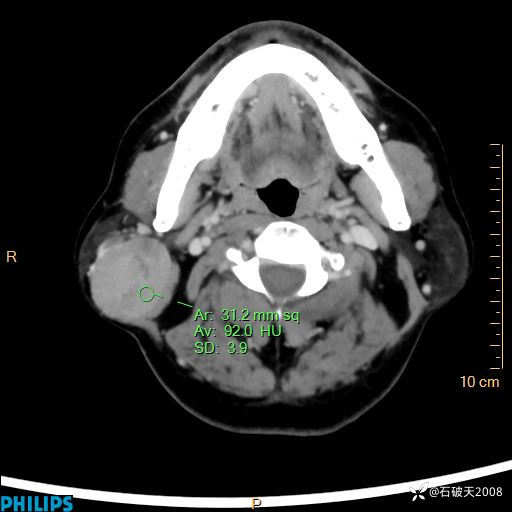

病例分享:颈部占位,一周后公布病理

男 57岁 主 诉:发现右侧颌下肿物1月余。

现病史:1月余前家属发现右侧颌下肿物。局部皮肤无红肿、热痛,无吞咽困难,无异物感,无恶心、呕吐,无头痛、头晕,无胸闷、胸痛,无发热、咳嗽、咳痰及呼吸困难。于我院行体表肿块彩超检查(2024.03.15我院)示:右侧耳下皮下软组织内低回声,未治疗。今为进一步治疗门诊以“腮腺肿瘤”为诊断收住我科,发病来患者神志清,精神可,饮食、睡眠及大小便正常,体重无明显下降。

MIP